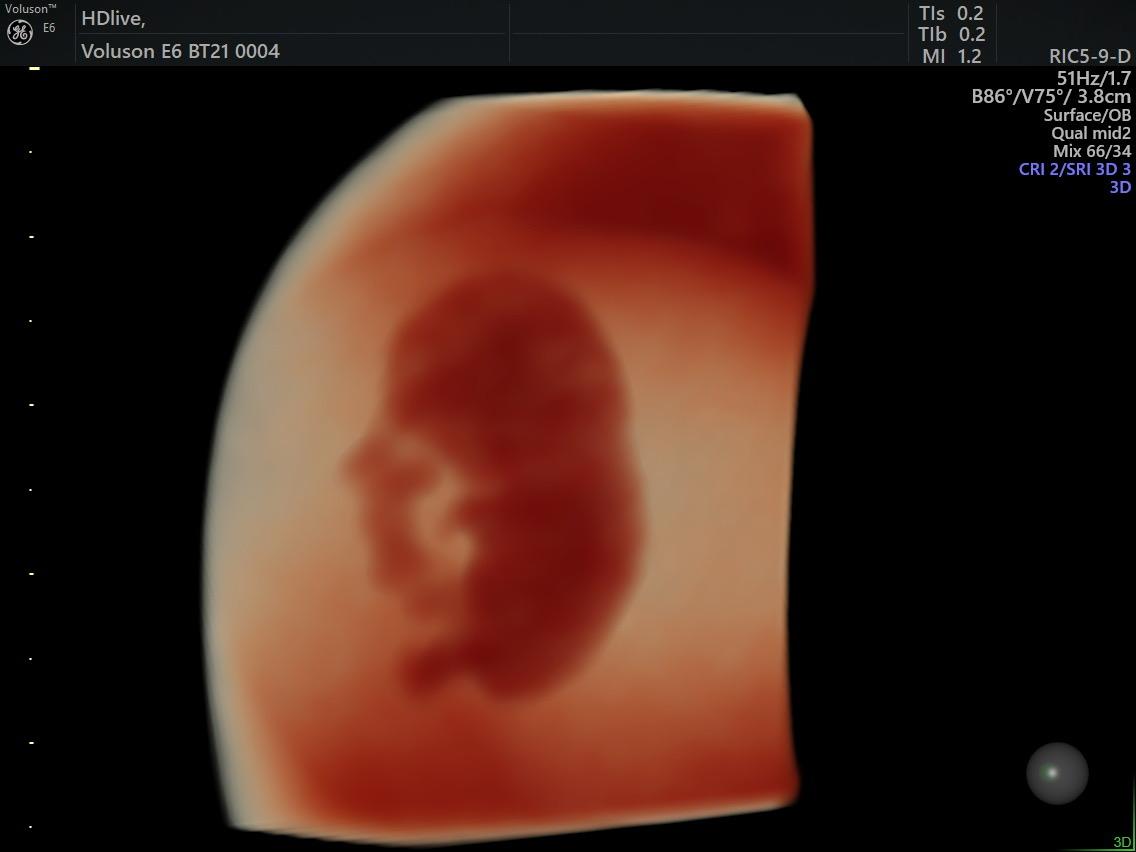

Fetal Medicine

Ultra Sound

Gallery

Images

Photos